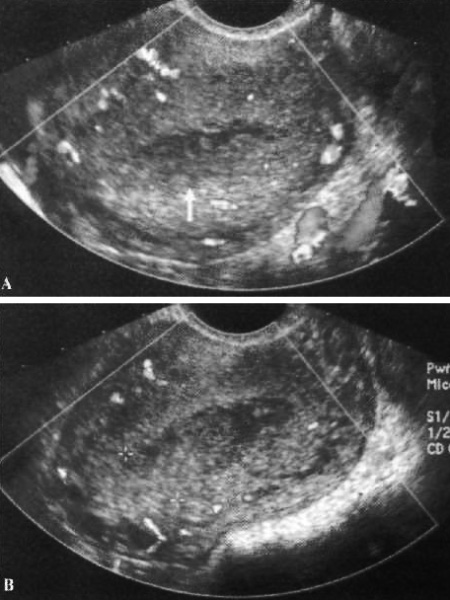

К типичным ультразвуковым признакам зрелой кистозной тератомы относится дермоидная пробка (узел Рокитанского) – специфичный эхогенный компонент, который может быть разного размера и является частью сочетанного образования, часто с наличием кистозного компонента, иногда наблюдаются локальные кальцификации. Основным содержимым зрелой кистозной тератомы является жир. Зрелая кистозная тератома может вызывать задержку звука, что затрудняет визуализацию более глубоких областей образования (фото 4).

Фото 4. Зрелая кистозная тератома. А – контуром обозначено правое образование придатка (эхогенное). В – компьютерная томограмма той же пациентки: стрелкой указано образование, что подтверждает диагноз зрелой кистозной тератомы

Двусторонние зрелые кистозные тератомы выявляют примерно в 10-15% случаев.